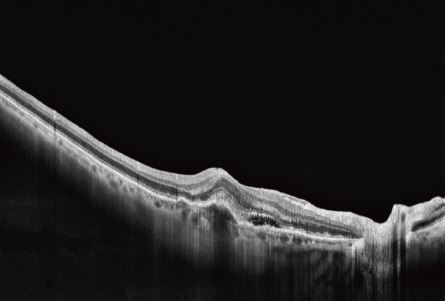

A tomografia de coerência óptica (OCT) oftálmica utilizada no BV1000S traduz-se num OCT de inteligência artificial totalmente automático com direitos de propriedade intelectual totalmente independentes. Combinado com tecnologia de registo e aperfeicoamento de imagens múltiplas e tecnologia de análise líder do setor, este OCT fornece uma solução completa para diagnóstico e tratamento clínico, incluindo captura automática, precisa e objetiva das imagens. Inclui também gestão inteligente de registo de saúde ocular e partilha de dados em tempo real na nuvem (cloud).